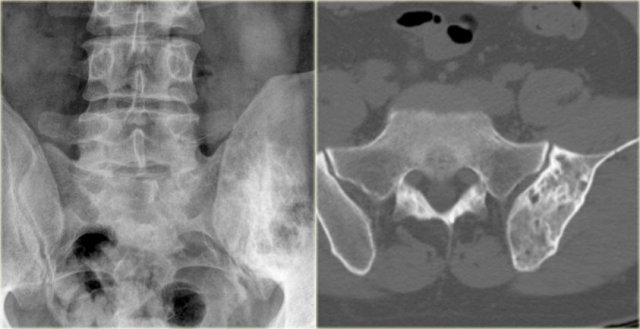

Fibrous dysplasia (7)

The radiograph on the left shows a mixed lytic-sclerotic lesion of the left iliac bone.

Axial CT image on the right shows some broadening of the iliac bone with a ground glass appearance and no cortical destruction.